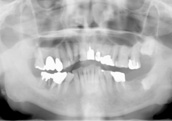

| これは、10年間メンテナンスなしで放置し症状が悪化した例です。 |

| <30歳代 男性> |

| 2008年6月 |

2017年9月 |